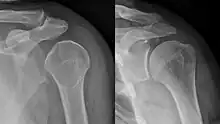

Anterior dislocation of the right shoulder. Y view X ray.

Fracture dislocation of the right shoulder